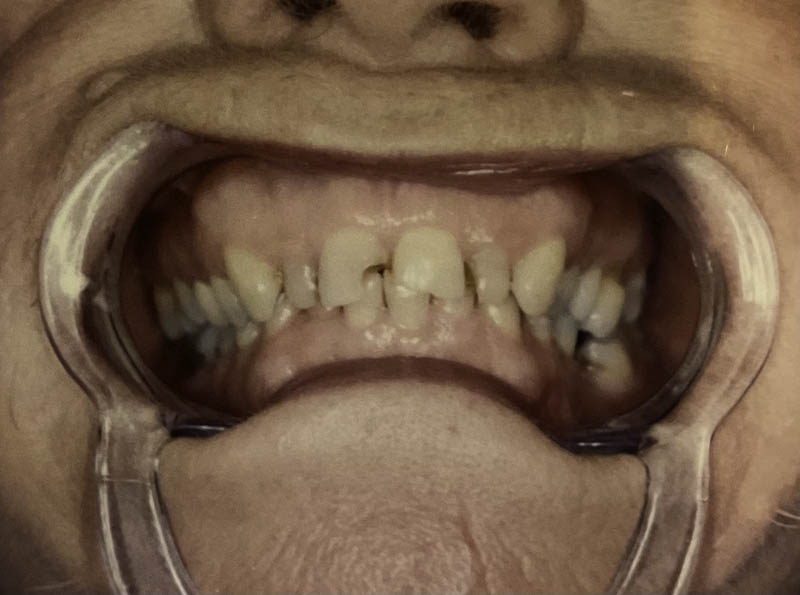

Before

After

Custom Cosmetic Crowns

Case Highlight